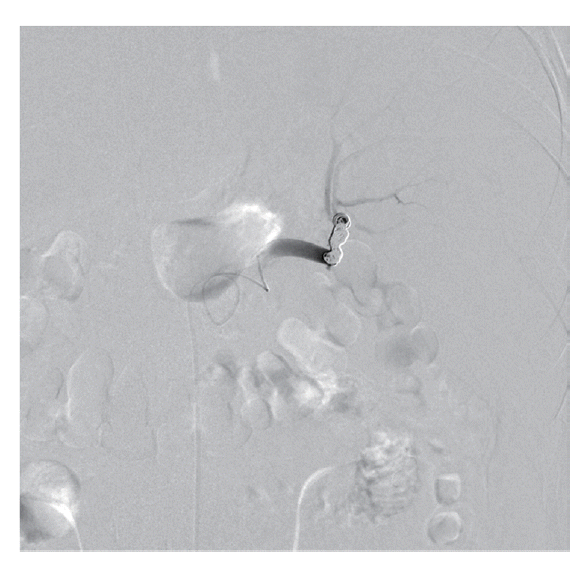

The patient’s hemoglobin level was 14.4 g/dl 1 day before visiting the Emergency Department and decreased to 11.0 g/dl. The concentration then rapidly dropped to 9.5 g/dl, and the patient received a blood transfusion. The patient also had thrombocytopenia (71 k/μl) with 33 IU/L AST, 44 IU/L ALT, 25.4 mg/dl BUN, and 1.66 mg/dl creatinine. He was admitted to the intensive care unit for a conservative treatment. Despite transfusion, the hemoglobin levels and blood pressure remained unstable. On the second day of hospitalization, a splenic angiogram was performed. No definitive extravasation of contrast media was observed, but contour irregularity was noted in the lateral lower margin (Fig. 3). Embolization was performed with 7 coils (10×4 mm, 8×4 mm, 6×2 mm; Cook, Bloomington, Minneapolis, USA) at the distal splenic artery level (Fig. 4).